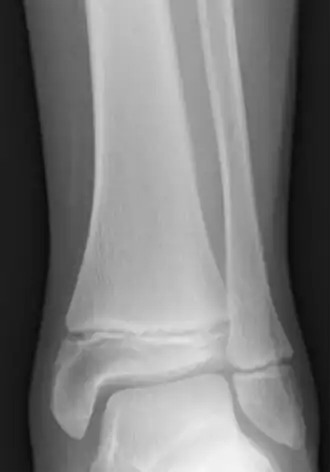

Je popsána celá řada různých nemocí spojených s růstovou ploténkou. Poměrně častou záležitostí je zlomenina kosti v oblasti růstové ploténky. Typ fraktury popisuje tzv. Salter-Harrisova klasifikace; v nejvážnějších případech může dojít až k zastavení růstu kosti. Dalším onemocněním je avaskulární nekróza postihující části kostí, které nejsou dostatečně prokrveny a umírají na nedostatek živin a kyslíku. Tento typ nekrózy může nastat např. v holenní kosti (Osgood-Schlatterova choroba), člunkovité kosti (Kohlerova choroba) nebo v páté kosti nártní (Uhkeho choroba). Jiným typem nekrózy je disekující osteochodritida (osteochondritis dessicans). Nastat však může i zánět, apofyzitida.[4]